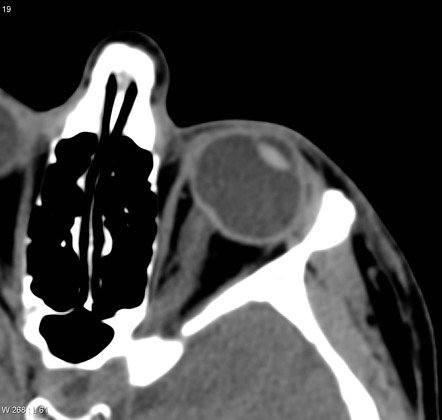

사상판 뒷부분에는 사상판후층(Retrolaminar region)이 있습니다.

이부분에는 사상판을 빠져나온 시신경섬유들이 주행하는 곳으로, 시신경 섬유들 주위에

마이엘린수초가 둘러싸이게되는 부분이며,

이때부터는 신경섬유주위에 별아교세포(astrocyte)들이 줄어듭니다.

<시신경 유두의 혈액공급>

사상판 전층(Pre-lamina cribrosa area)은...

맥락막을 공급하는 Short posterior cilliary a와

시신경 유두 주위의 둥근 혈관망인 Circle of Zinn-haller 에 의해서 공급을 받습니다.

사상판 중격 그자체는 Short posterior ciliary a 와

때로는 Circle of Zinn-Haller 에 의해서 공급을 받습니다.

사상판 후층의 경우 연질막 현관(Pial vs)과 망막혈관 (Central retinal artery)로부터 혈액 공급을 받습니다.